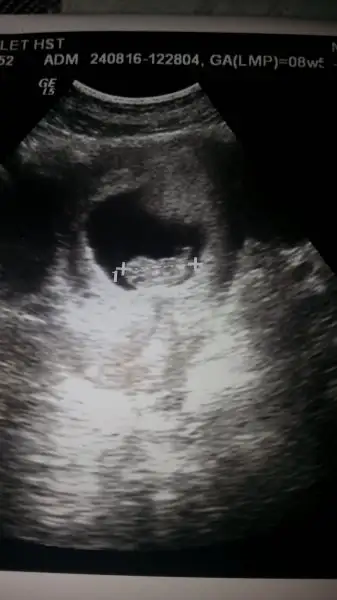

Çok anlamam ama içimden kız geçtiMerhaba arkadaslar iyi bayramlar yorum yapabilir misiniz 8 haftalik karından cinsiyet belli gibi bakalim